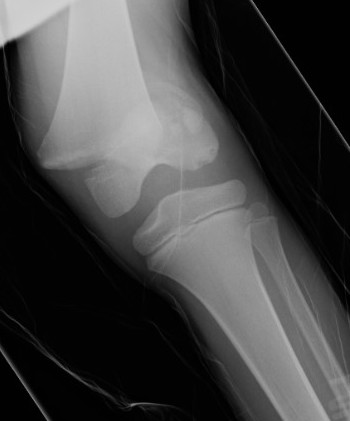

Distal Femoral Fracture SH2 APDistal Femoral Fracture SH2 Lateral

Salter Harris Type II